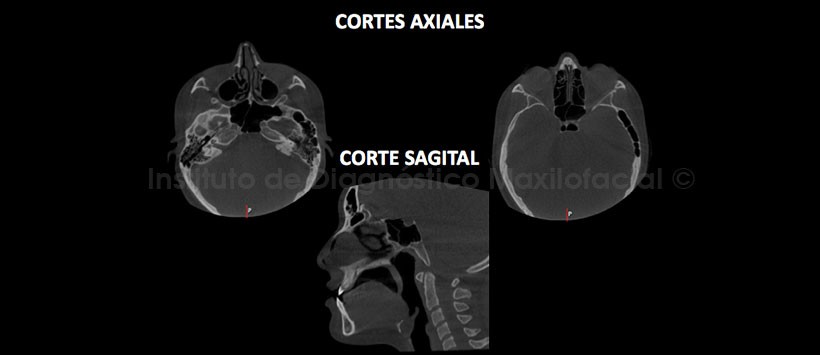

A la evaluación de la tomografía volumétrica (CBCT) en cortes axiales, sagital (Figura 3) y coronales (Figura 4), se evidencia la neumatización del seno esfenoidal, a predominio del lado izquierdo, compromemtiendo las apofisis clinoides anterior y posterior, se aprecia tambien la neumatización de las celdillas mastoideas del lado izquierdo (Figura 5) que se extiénde a la porción escamosa y petrosa del hueso temporal, con presencia de multiples tabicaciones.